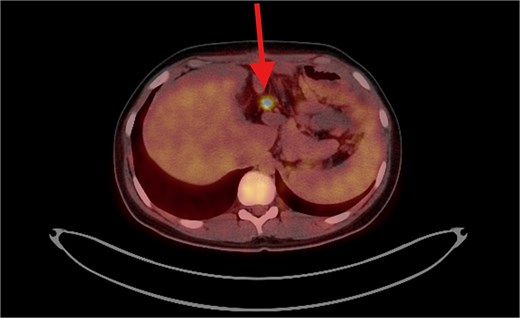

The patient underwent left lateral hepatectomy and cholecystectomy following diagnosis. Histopathology confirmed undifferentiated embryonal sarcoma (UES) of the liver with a 1 mm clear margin (Fig. 1); immunohistochemistry supported the diagnosis. The gallbladder showed chronic cholecystitis, and the lymph nodes were tumor-free. Postoperative imaging after two months revealed a recurrent mass near the stomach (Fig. 2), confirmed as recurrent UES by biopsy. Re-excision showed extensive necrosis and peritoneal infiltration. Positron emission tomography – computed tomography (PET-CT) later identified peritoneal and mesenteric metastases (Fig. 3). Follow-up PET-CT also revealed multiple small hypermetabolic hepatic nodules in addition to peritoneal and mesenteric lesions, indicating intrahepatic disease recurrence. Six cycles of chemotherapy resulted in near-complete resolution of metabolic lesions, with minimal residual activity. Follow-up imaging showed near-complete resolution of hepatic nodules, with only one residual, non-suspicious tiny nodule. After additional chemotherapy and targeted therapy cycles, PET-CT revealed new focal hypermetabolic activity near the splenic flexure, anterior to the spleen, raising concern for recurrence (Fig. 4). The patient underwent omentectomy and splenectomy. Histopathology confirmed metastatic UES in a 2.5 cm splenic lesion with hemorrhage and necrosis, and a 0.4 cm omental nodule, both completely excised. A total of 15 chemotherapy cycles were completed. Post-treatment imaging showed a mixed-density lesion in the splenic bed with FDG uptake, possibly post-surgical, and a new hypermetabolic mesenteric nodule (Fig. 5). Magnetic resonance imaging showed a cystic post-surgical collection without enhancing lesions. Subsequent imaging revealed regression of the splenic bed lesion and resolution of the mesenteric nodule; however, a new hypermetabolic mesenteric density emerged (Fig. 6). The lesion was placed under active surveillance, with additional chemotherapy administered and repeat imaging scheduled to assess response. Bilateral axillary lymph nodes showed reactive hypermetabolism. The patient, having undergone hepatectomy, splenectomy, and multimodal therapy, remains under close surveillance with encouraging treatment response.

PET/CT scan shows a clear surgical site (left subphrenic area) with no residual/recurrent mass, but there are multiple peritoneal and mesenteric nodules which appear to be hypermetabolic on PET scan, suggesting secondary metastasis.